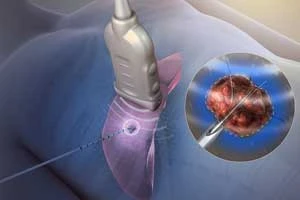

Radiofrequency Ablation (RFA)

Catheter-based treatment for abnormal heart rhythms

Radiofrequency Ablation (RFA)

Catheter-based treatment for abnormal heart rhythms